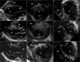

Cardiac rhabdomyoma

A rhabdomyoma is a benign tumor of striated muscle. Rhabdomyomas may be either "cardiac" or "extra cardiac" (occurring outside the heart). [Source: Wikipedia ]